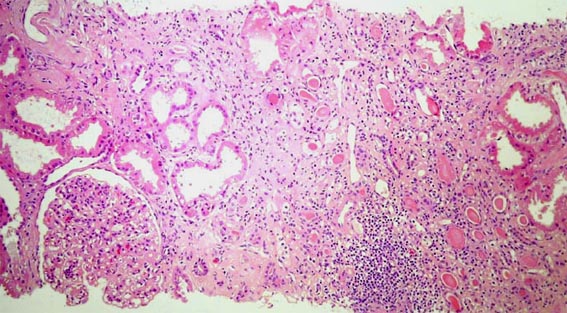

Figure 1.

H&E, X100.